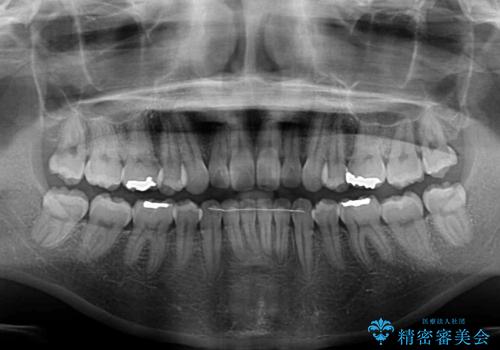

抜歯矯正の後戻り インビザライン・ライトによる矯正治療

- 矯正治療の後戻りを気にして来院された患者様です。

後戻りは軽微であったので、インビザライン・ライトにより矯正治療を行うこととしました。

治療途中、妊娠・出産があり、1年近く治療が停滞しましたが、無事に終了することができました。

インビザライン・ライトは提供されるマウスピースの数に制限があり、通常のタイプよりもマウスピース提供期間が短くなっている一方、安価に治療を行うことができるプランです。

治療のゴールも変更できないため、軽微な歯列不正や、後戻り改善などに適しています。